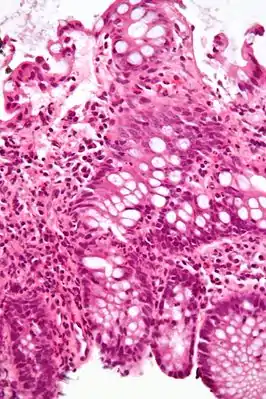

Коли́т (лат. colitis; от греч. kolon — толстая кишка и греч. itis — воспалительный процесс) — воспалительное заболевание слизистой оболочки толстой кишки. Чаще болеют мужчины 40—60 лет и женщины 20—60 лет. Протекает остро или хронически. Считают, что проявления хронического колита имеют место у каждого второго больного с проблемами органов пищеварения. К колитам предрасполагают снижение общей резистентности организма, недостаток растительной клетчатки в пище, воспалительные болезни аноректальной зоны (восходящая инфекция).

Диагноз колита основывается на типичных жалобах, сборе анамнеза (перенесенный гастроэнтероколит, пищевая токсикоинфекция и др.), физикальном обследовании (пальпация живота, пальцевое исследование, аноскопия), инструментальных методах (эндоскопия, ректороманоскопия и ирригоскопия с введением контраста — сульфата бария) и лабораторных данных. Инструментальные методы позволяют визуально контролировать состояние слизистой оболочки, и дифференцировать обычный колит от язвенного колита.